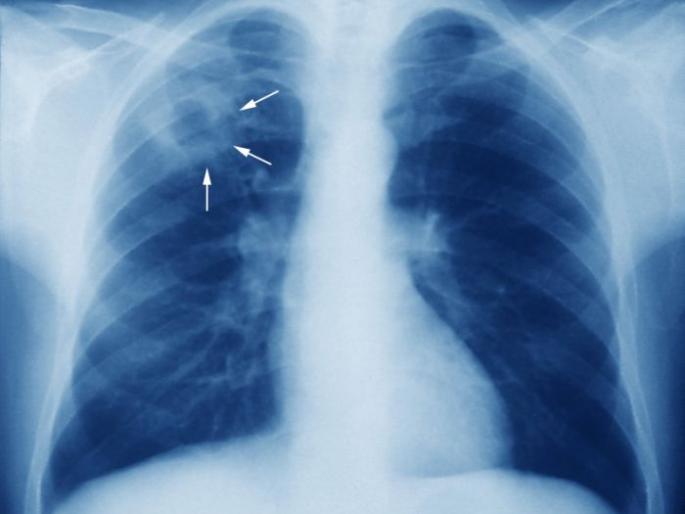

नागपूर : क्षयमुक्त भारत करण्यासाठी देशामध्ये सर्व स्तरातून प्रयत्न करण्यात येत असून, राष्ट्रीय क्षयरोग नियंत्रण कार्यक्रम नॅशनल स्टेटस् प्लॅन सन २०१५ ते २०१७ कार्यक्रमांतर्गत क्षयरोगाचे प्रमाण कमी करण्याच्या व त्यामुळे होणारे मृत्यू रोखण्याच्या दृष्टिकोनातून १६ मार्च २०१८ ची अधिसूचना लागू करण्यात आलेली आहे. याअंतर्गत प्रत्येक रुग्णालयाने क्षयरुग्णांची नोंदणी करणे बंधनकारक करण्यात आले असून, जिल्हा क्षयरोग अधिकारी कार्यालयामार्फत रुग्णांच्या नोंदणीसाठी आवाहन करण्यात आले आहे. तसे न केल्यास रुग्णालयांना शिक्षेची तरतूदही आहे.